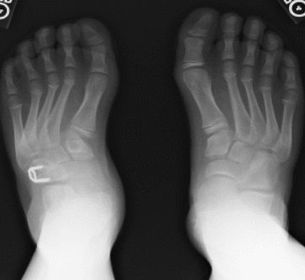

| What is this? | Os Intermetatarseum |

| What angle is this? Is this normal or abnormal? | 1st intermetatarsal angle Abnormal. Greater than 9 degrees is abnormal. Usually due to metatarsus primus varus |

| What deformity is this? | Metatarsus Adductus |